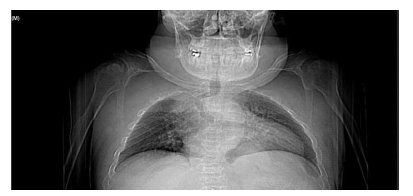

En la bibliografía se describe con detalle los defectos del esmalte que presentan los pacientes diagnosticados del síndrome de Morquio. Estos defectos son una característica aparentemente constante en la enfermedad y, por lo tanto, hace necesaria las visitas al odontólogo para su control evitándose problemas mayores. Dichos defectos consisten en un esmalte anormalmente delgado, que es áspero debido a los numerosos hoyos diminutos y a una superficie irregular. La delgadez del esmalte da como resultado una forma alterada y decoloración de los dientes que, añadido a los diastemas interdentales, provocan alteraciones en la oclusión. Aparte de estos defectos, el esmalte es histológicamente normal y tiene una dureza y radiodensidad normales. El tratamiento odontológico de los pacientes con MPS-IV requiere colaboración multidisciplinar, debido a que las manifestaciones orales de la enfermedad pueden aparecer a cualquier edad, resultando en ocasiones tedioso para el paciente y complicado para el profesional. Especial mención merecen las terapias utilizadas como tratamiento sintomático de la enfermedad, así como el manejo de la vía aérea en el caso de intervenciones bajo anestesia general o sedación para tratar ciertas patologías del territorio bucomaxilodental.

The enamel defects presented by patients diagnosed with Morquio syndrome are described in detail in the bibliography. These defects are an apparently constant feature in the disease and, therefore, make visits to the dentist necessary for their control, avoiding major problems. These defects consist of an abnormally thin enamel that is rough due to numerous tiny holes and an irregular surface. The thinness of the enamel results in an altered form and discoloration of the teeth, which added to the interdental diastemas, cause alterations in the occlusion. Apart from these defects, the enamel is histologically normal and has a normal hardness and radiodensity.

Dental treatment of patients with MPS-IV requires multidisciplinary collaboration, because the oral manifestations of the disease can appear at any age, being sometimes tedious for the patient and complicated for the professional. Special mention should be made of the therapies used as a symptomatic treatment of the disease, as well as the management of the airway in the case of interventions under general anesthesia or sedation to treat certain pathologies of the bucomaxillodental territory.